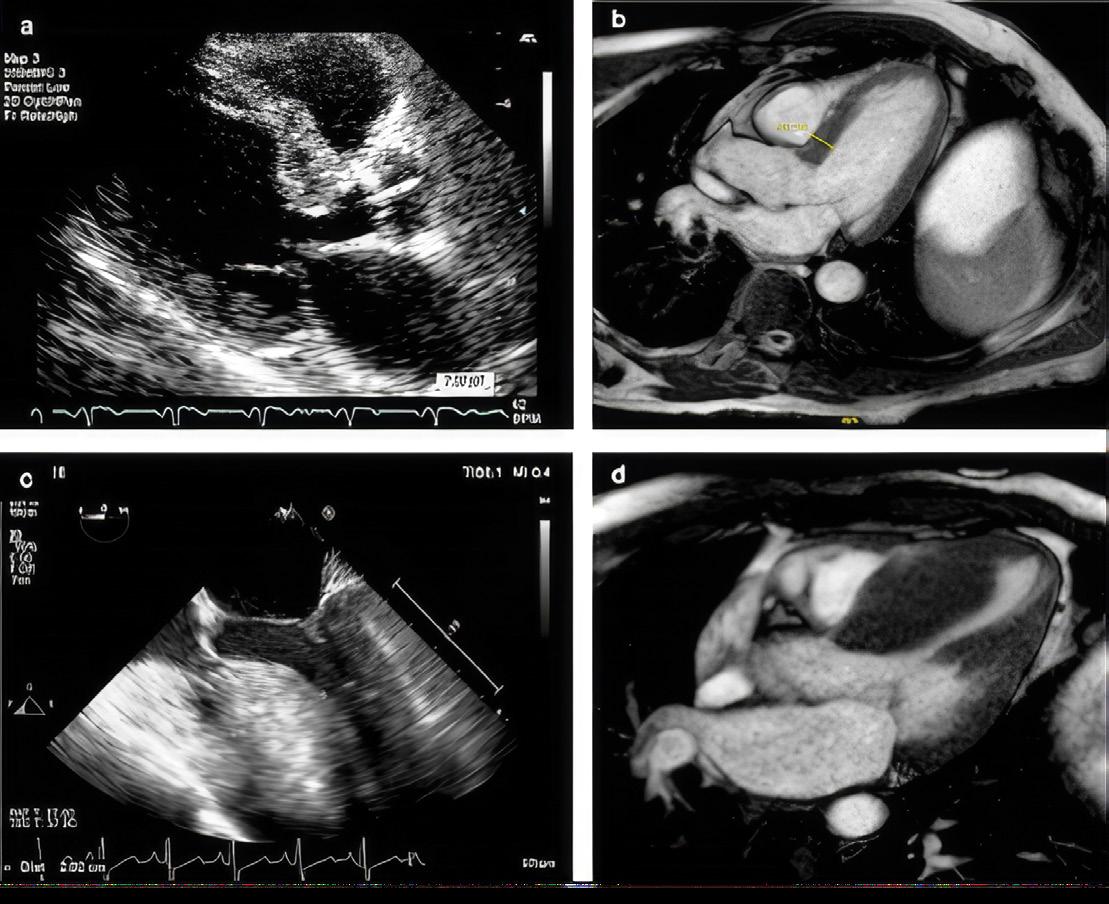

Cardiac computed tomography showing HCM with severe hypertrophy.

CMR is best suited to distinguish mimics or phenocopies of HCM that include physiologic conditions like athlete’s heart and pathologic conditions like cardiac amyloidosis (CA) and Fabry disease (FD). This is an essential first step to verify a patient has HCM. The management of these conditions is vastly different.

Transthoracic echocardiography (TTE) is the first-line diagnostic test in the evaluation of HCM. TTE is not specific for the diagnosis of HCM but it helps exclude other structural abnormalities that cause increased LV wall thickness, including a subaortic membrane and aortic valve stenosis. TTE findings typical of HCM include increased LV wall thickness, systolic anterior motion of the mitral valve, LV outflow tract obstruction (LVOTO), abnormal diastolic function and abnormal myocardial deformation or strain. CMR is usually performed following an abnormal TTE indicative of HCM.

A comprehensive multi-parametric CMR examination allows for confirmation of HCM, characterization of morphology and severity of hypertrophy, assessment of LV function, exclusion of phenocopies, and information for SCD risk stratification. The protocol must include imaging with gadolinium contrast media. CMR cine imaging improves detection of hypertrophied segments and allows accurate measurement of wall thickness. T1-mapping has emerged as a valuable tool for myocardial tissue characterization which helps differentiate HCM, CA and FD (Figure 1). Late gadolinium enhancement (LGE) imaging allows detection of interstitial fibrosis (Also